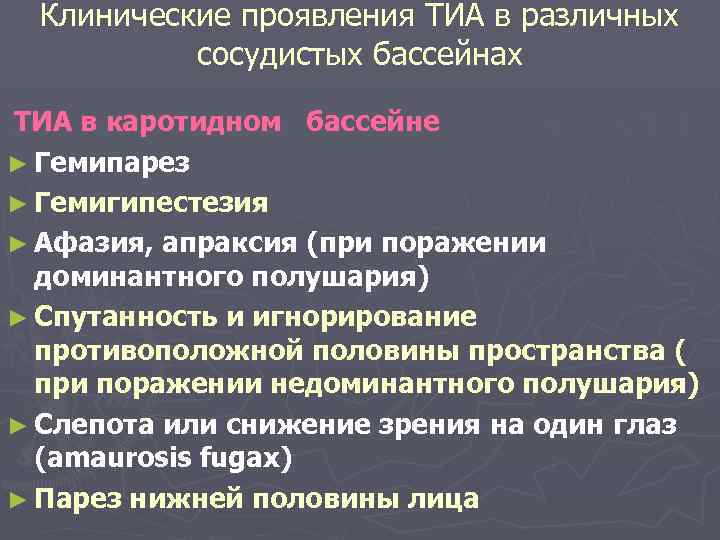

Клинические проявления ТИА в различных сосудистых бассейнах ТИА в каротидном бассейне ► Гемипарез ► Гемигипестезия ► Афазия, апраксия (при поражении доминантного полушария) ► Спутанность и игнорирование противоположной половины пространства ( при поражении недоминантного полушария) ► Слепота или снижение зрения на один глаз (amaurosis fugax) ► Парез нижней половины лица